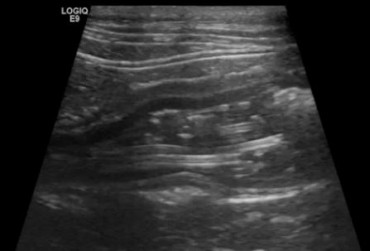

Zarażenie psa pasożytem nicieniem Dirofilaria immitis – opis przypadku

W artykule opisano przypadek dirofilariozy u psa wywołanej D. immitis. U badanego pacjenta stwierdzono patognomiczny obraz zmian w badaniu rentgenowskim i ultrasonograficznym układu sercowo-naczyniowego.